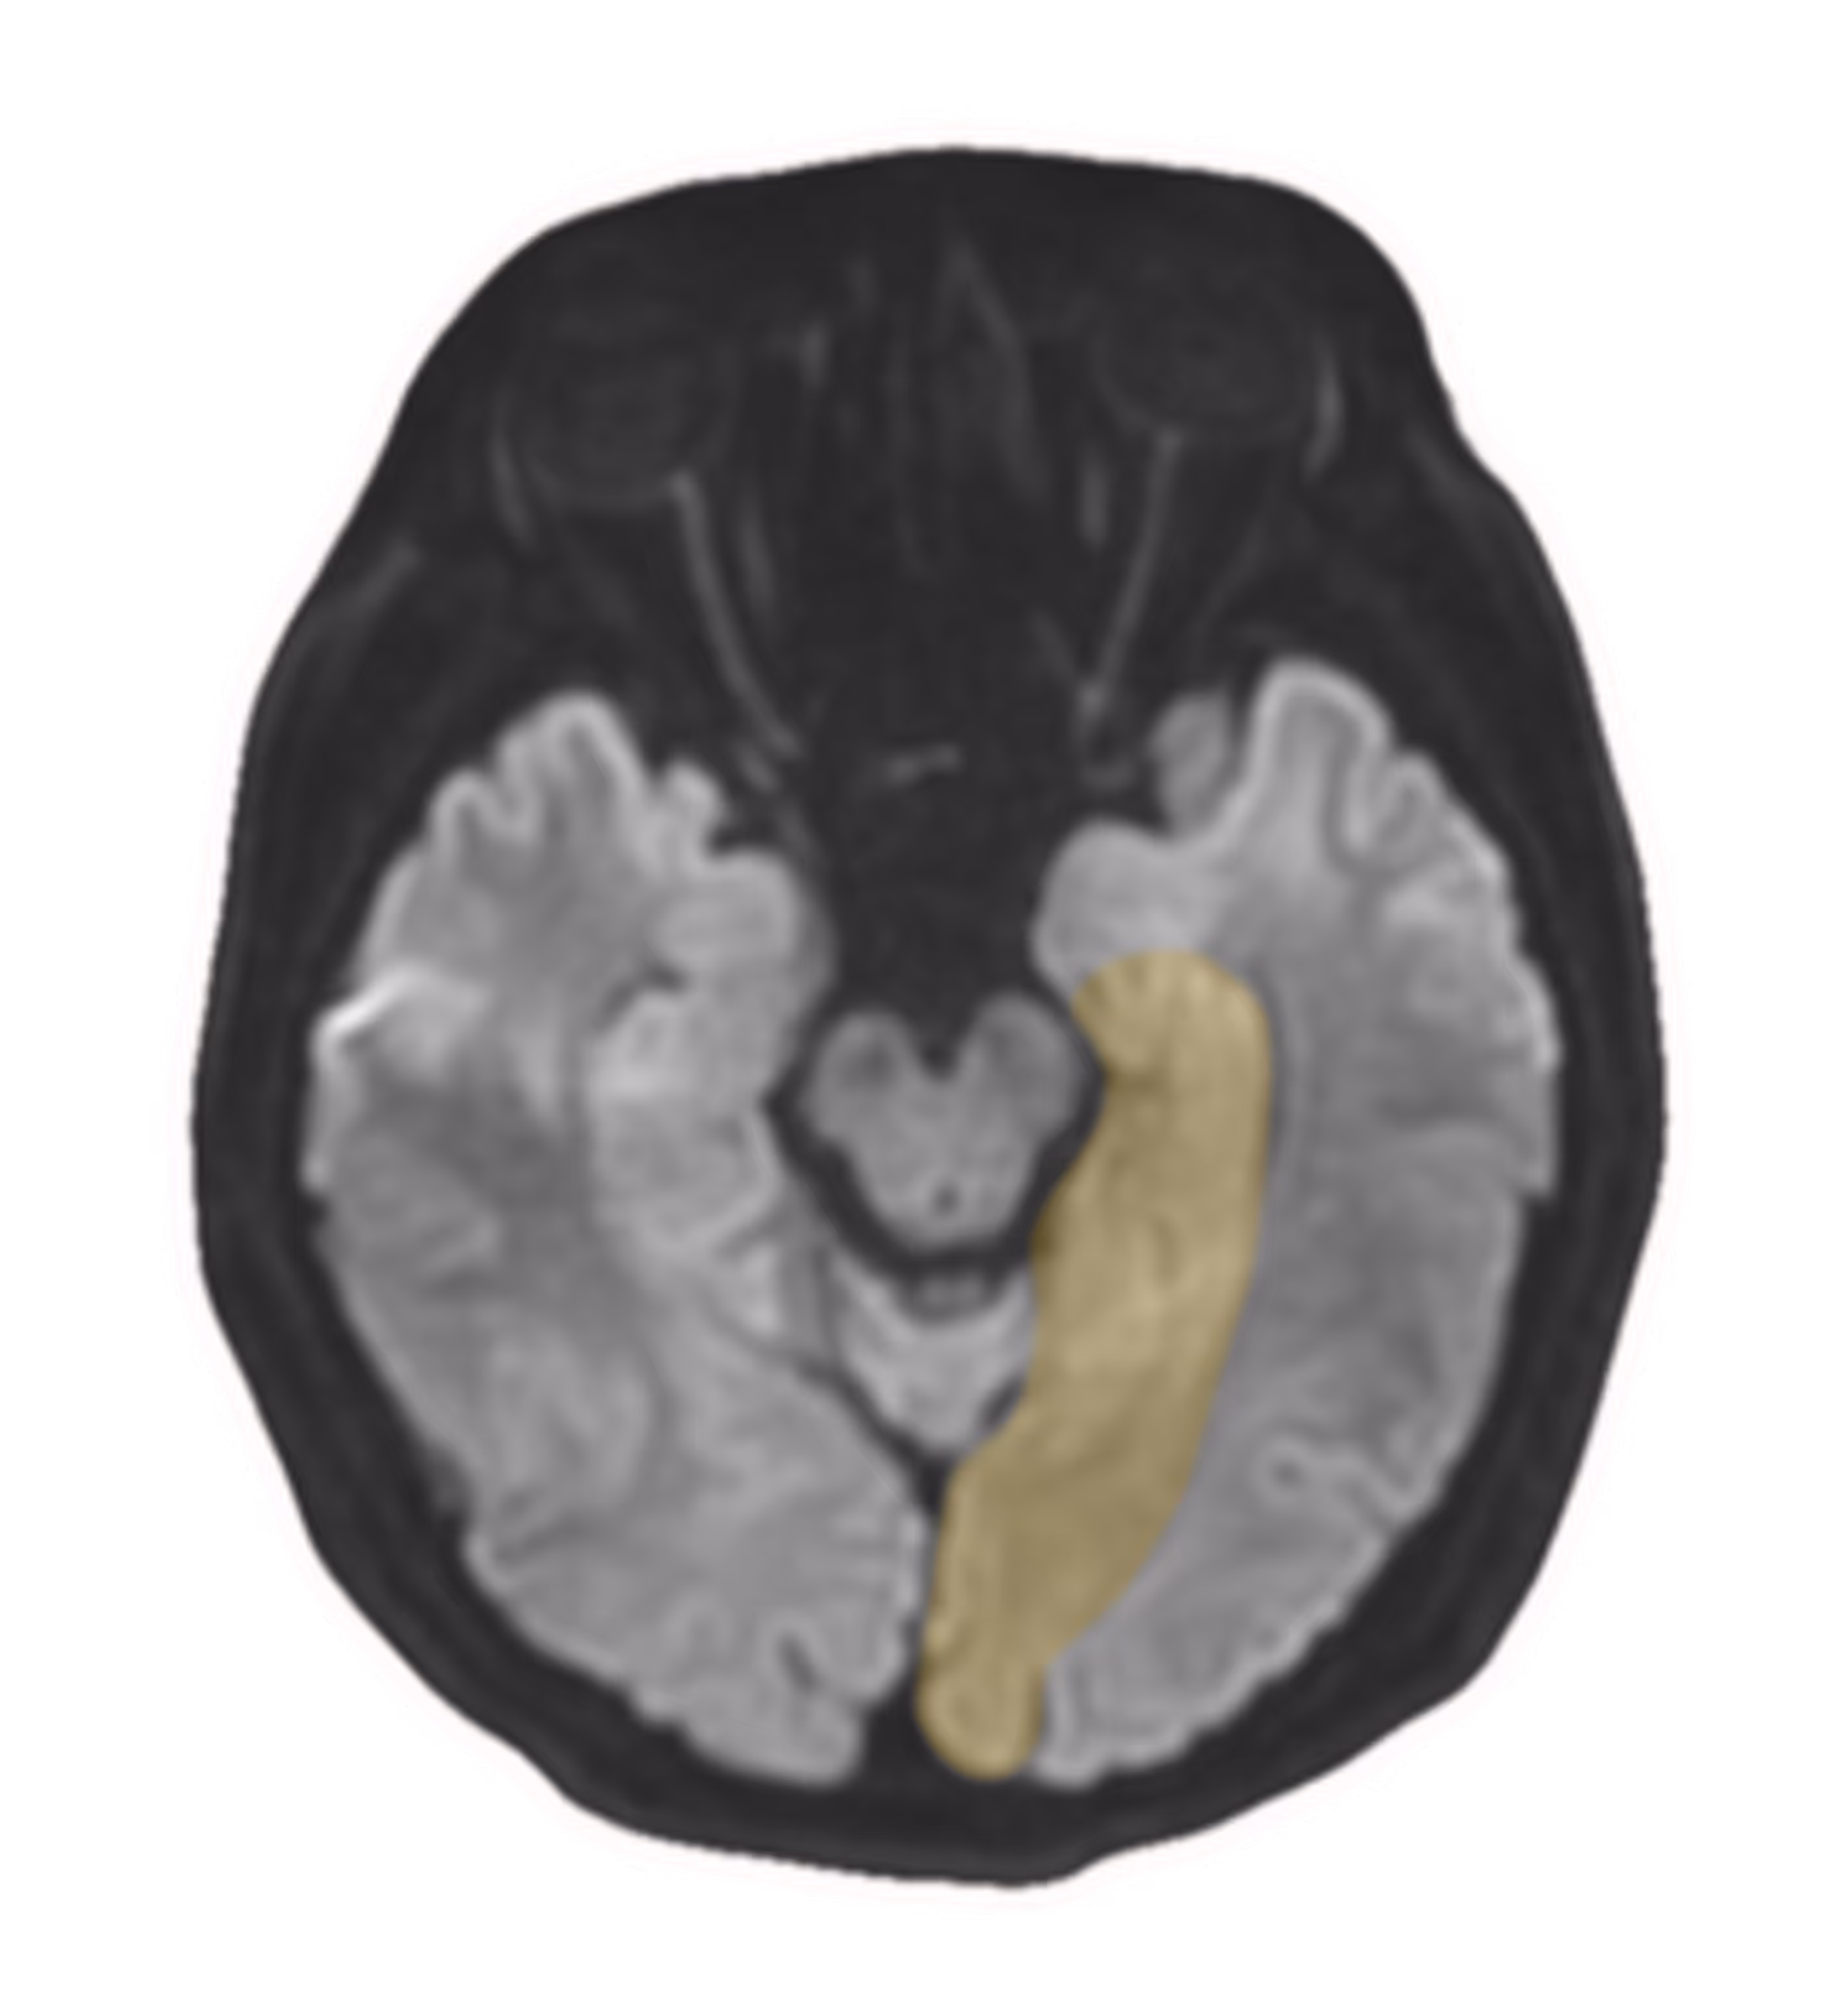

The app seeks to offer an intuitive and interactive approach to the radiology of transient global amnesia (TGA), a condition that presents unique imaging features for medical students/interns.It includes a hands-on tutorial that guides users in analysing radiological images of brain regions affected by TGA. The tutorial guides users from foundational concepts to pathophysiology, and differential diagnoses.

Example case study